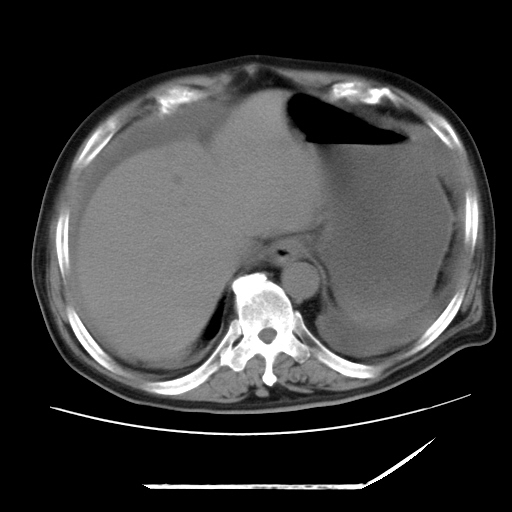

以下是引用zxl51642在2009-8-12 18:55:00的发言:[br]1、肠系膜脂肪浑浊,密度增高,腹水,支持腹膜炎诊断;2、右肾盂及输尿管中段结石,左输尿管起始段结石;3、胆囊切除术后改变?4、双侧胸膜腔少量积液;5、胰腺体积不大,勾勒清楚,肾前筋膜无增厚,不支持胰腺炎,请结合血尿淀粉酶及临床。